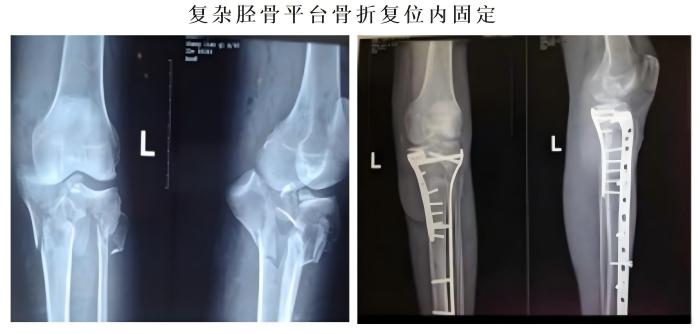

常规开展人体各部位骨折、脱位的修复重建。业务亮点:①跳蛋视频

骨科对于复杂胫骨平台的治疗方法获得国际“平台大师”罗从风教授的高度肯定,并将其编入胫骨平台骨折诊疗教程。②跳蛋视频